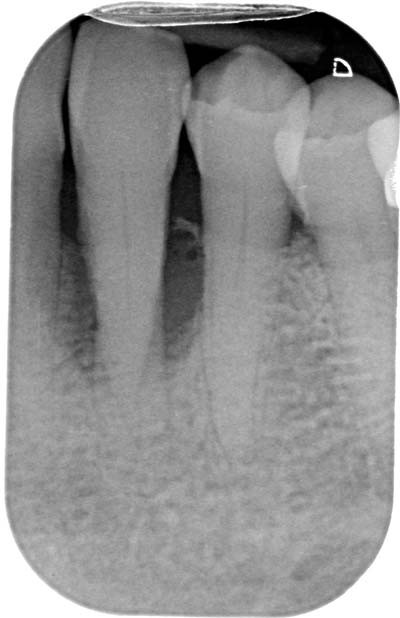

Le diagnostic différentiel avec la lésion d’origine endodontique et la lésion endo-parodontale devra s’appuyer sur le sondage, le test de vitalité et l’examen radiographique par radio rétro-alvéolaire. En cas de lésion d’origine parodontale, le sondage est arciforme, le test de vitalité est positif et une image radio-claire latérale peut être observée sur le cliché rétro-alvéolaire (tableau 1, fig. 2).